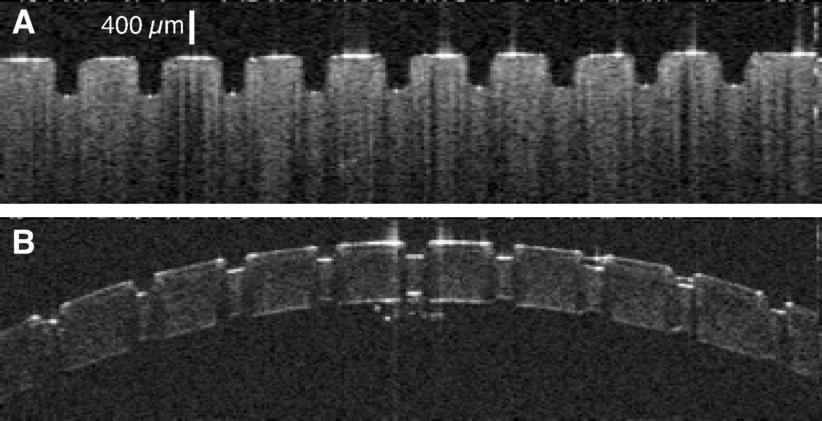

OCT images of ablation craters in (A) gelatin and (B) cornea created by the Raman-shifted alexandrite laser.

The goal of delicate neurosurgical and ophthalmic procedures is often to remove or ablate a defined volume of tissue while leaving surrounding tissue undamaged. There are several laser systems that can achieve this task, including mid-infrared Free Electron Lasers (mid-IR FELs). The Vanderbilt FEL was in fact used in several successful human surgeries. Despite this success, FELs are unlikely to ever find widespread use in patient care – due to both cost and size constraints. One of the major challenges in the field has been to translate the surgical successes of mid-IR FELs to cost-effective, compact, and dedicated medical laser systems. This challenge became even more pressing with the demise of funding for the Department of Defense Medical FEL Program and decommissioning of the Vanderbilt FEL. My group has taken the perspective that meeting this challenge requires a deeper physical understanding of mid-IR tissue ablation. We have thus investigated the details of tissue removal during mid-IR laser ablation – including the use of molecular spectroscopy (FTIR, micro-Raman, 13C-NMR, scanning electron microscopy, as well as UV and vibrational circular dichroism) to unravel exactly how tissue structural integrity fails – and found that the failure modes could be influenced by laser wavelength, pulse structure and spot size. We took these insights to a willing and able industrial collaborator, Light Age Inc, who designed and fabricated a prototype Raman-shifted alexandrite laser that operates in the mid-IR’s 6-µm wavelength region, with pulsewidths in the 10-ns regime and pulse energies of several mJ. Initial experiments in collaboration with Dr. Karen Joos in Ophthalmology showed that this laser ablates excised soft tissues as cleanly and efficiently as the FEL. Follow this link to learn more . . .